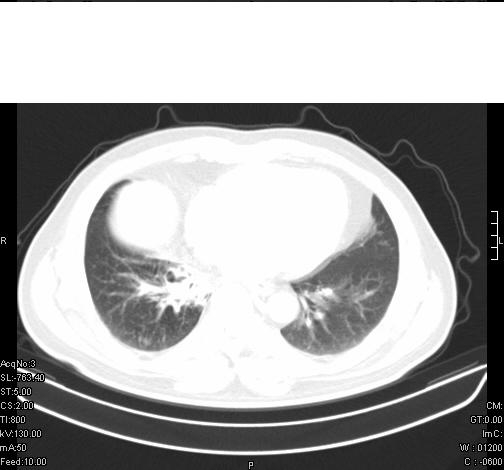

标题: CT6685:右肺阻塞性炎症,增强CT。

前几天,发了患者的平扫片,患者抗炎一周后增强扫描。右中叶病灶吸收明显,但下叶病灶未见明显吸收。右肺门可见结节影,看来凶多吉少

右肺下叶支气管管腔狭窄,管壁增厚,右下肺见斑片状高密度影,考虑右侧肺门中心肺癌伴阻塞性肺炎

右肺下叶散在的斑片状致密影,下叶支气管变窄。考虑:右肺慢性炎症。

支持:右肺下叶散在的斑片状致密影,下叶支气管变窄。考虑:右肺慢性炎症。

右肺下叶支气管壁不规则增厚,右肺下叶有斑片状影分布。考虑右肺中央型肺癌伴右肺下叶阻塞性改变。建议支纤镜检查。平扫比增强较好显示了病变情况。

既然抗炎治疗有效,可继续治疗;右肺下叶支气管管腔狭窄,管壁增厚,右下肺见斑片状高密度影,右侧主支气管后见结节影(淋巴结?),肺癌不能排出。